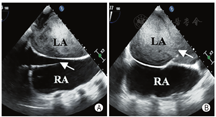

心房分流器置入过程的超声引导与监测:手术开始前,经食管超声多切面观察,排除心腔内血栓、房间隔缺损及房间隔膨胀瘤,同时再次确定适应证。术中经食管超声引导下,房间隔穿刺鞘沿导丝进入右房(图3A),穿刺鞘尖端于卵圆窝后下部进行穿刺(图3B)。穿刺后,预先塑形的加硬钢丝经房间隔穿剌部位至左心房内,其后递送10 mm外周动脉球囊至房间隔处,以8个标准大气压行反复球囊扩张。超声实时监测扩张部位、过程、大小。退出球囊后送入输送系统,选择20-6 mm的D-shant心房分流器,在经食管超声监测下,将其释放于房间隔两侧(图4A,B),经食管超声显示分流器形态、位置正常,分流孔径约6 mm,并清晰显示左向右分流信号(图5),三维超声观察分流器形态及其与周围组织毗邻关系;即刻右心导管测压,左房压由分流器置入前15 mmHg降至置入后8 mmHg(1 mmHg=0.133 kPa),释放分流器。术后送监护病房观察。患者自诉症状明显改善,1 d后从监护室转回普通病房,3 d后出院。3个月后复查心脏超声,分流器形态位置正常,患者自觉生活质量提高。